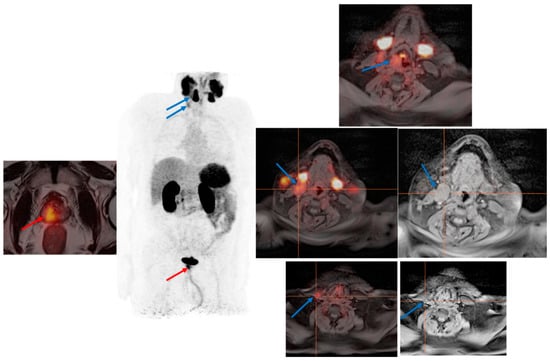

2. Clinical Report of the PSMA PET Scan

3.2. PSMA PET in Biochemical Recurrence PCa

3.3. Evaluation of PCa Patients for Possibility of PSMA Radioligand Therapies